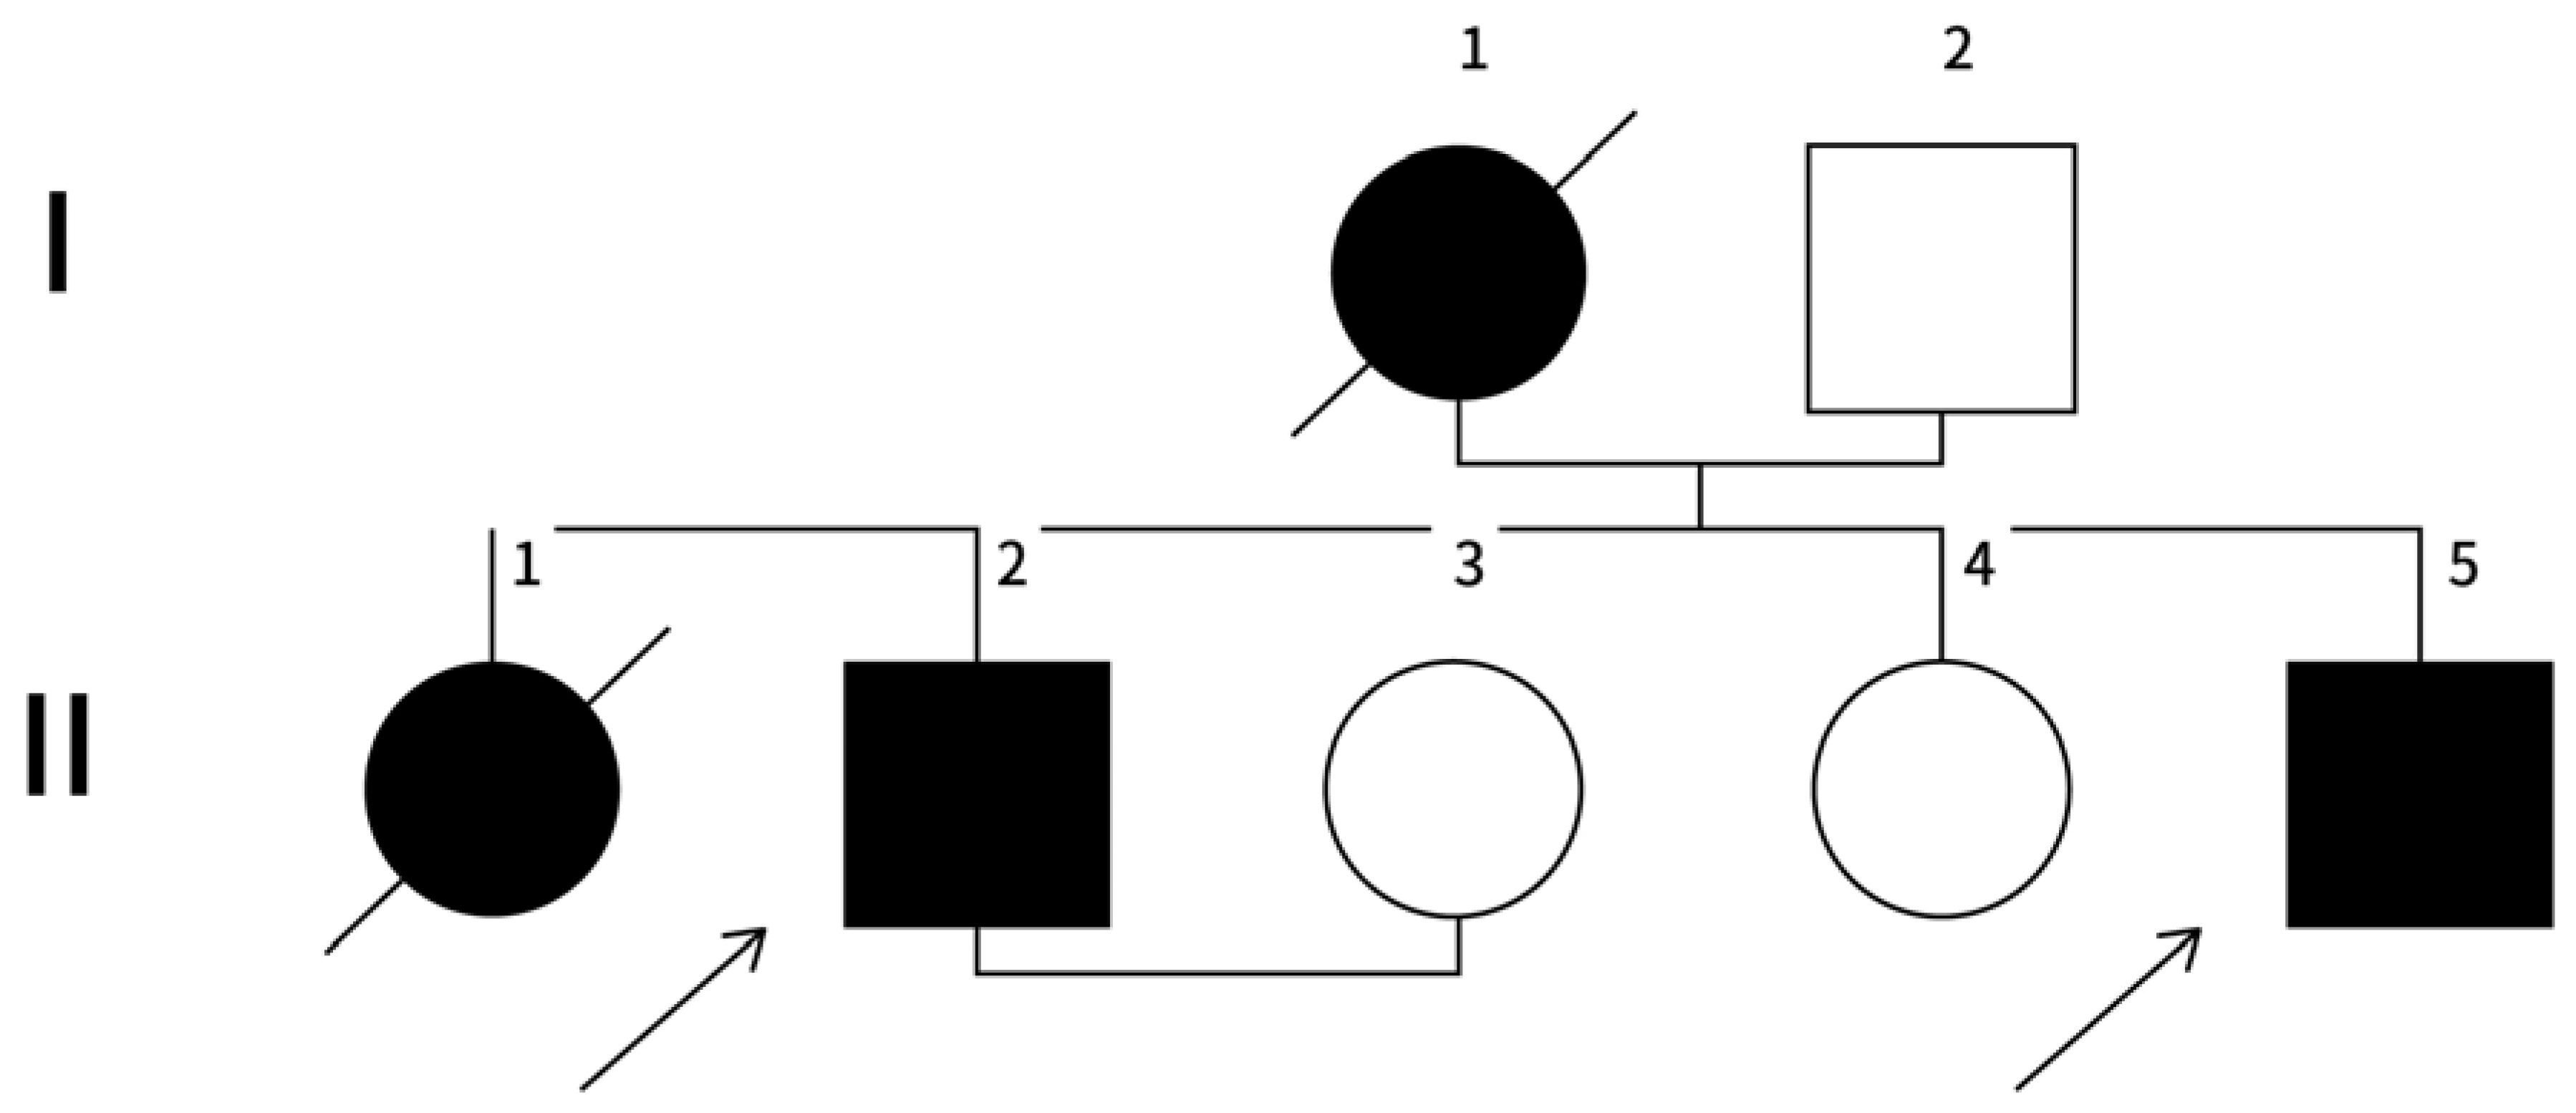

Family History